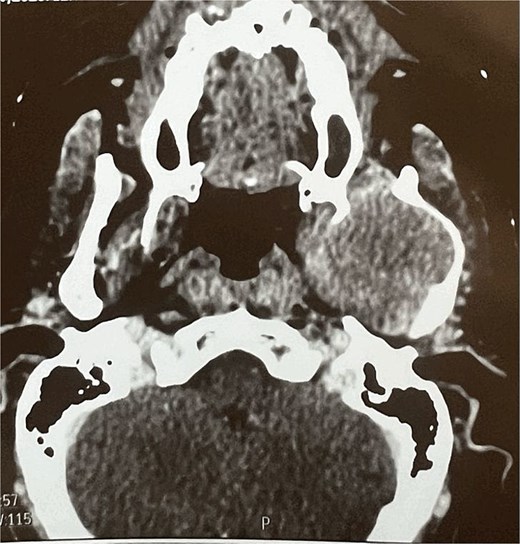

A facial CT scan shows a lesional process occupying the left infratemporal space, which is oval in shape, well-defined, and spontaneously isodense, with a calcified area and fine serpiginous vascular structures. It demonstrates heterogeneous enhancement after contrast injection (Fig. 5).

Facial MRI revealed a heterogenous soft tissue lesion in the infratemporal fossa measuring 47 × 51 × 53 mm, with imaging characteristics suggestive of a schwannoma of the third branch of the left trigeminal nerve.